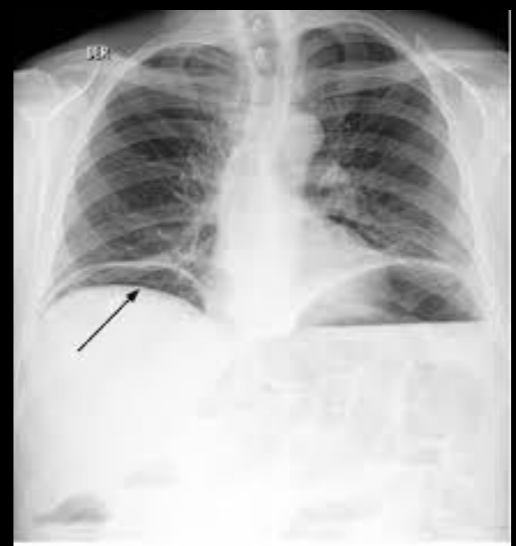

A

Pneumopericardio

Perforación